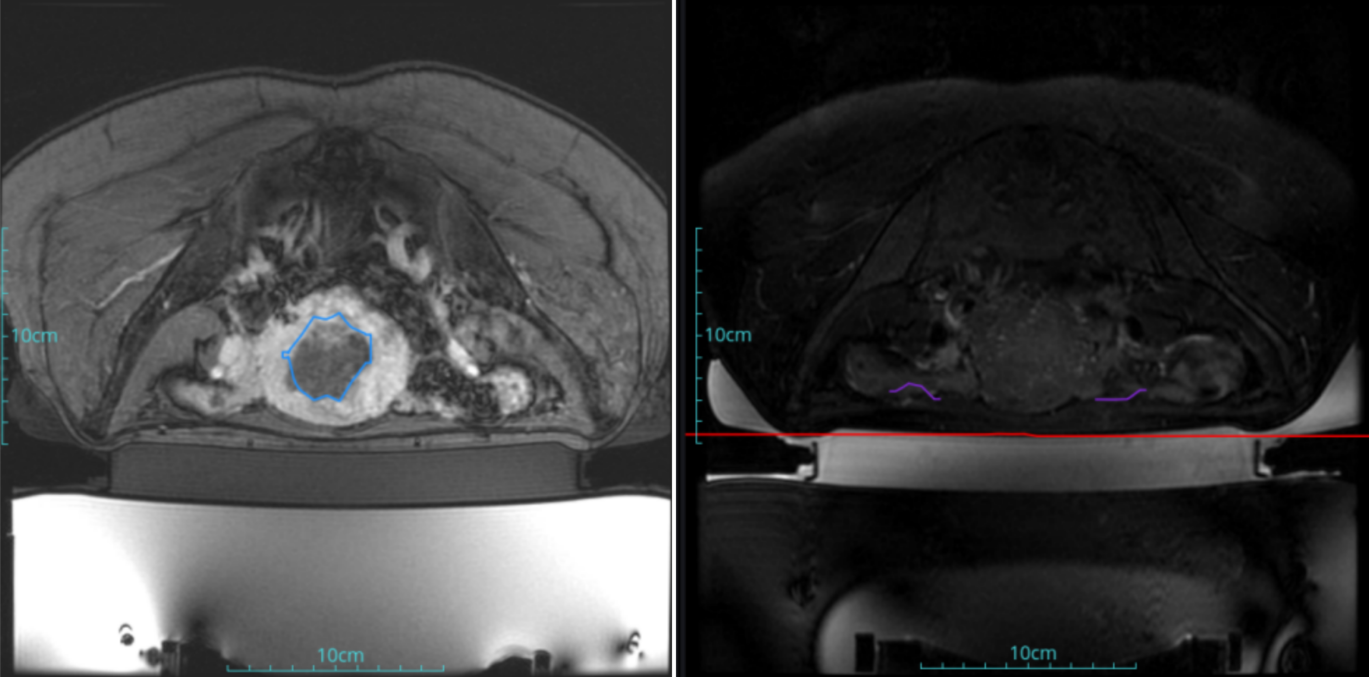

Uterine fibroids

Patient Information:Female,38

Diagnosis: Uterine fibroids

Tumor size: about 38*40*42mm

ROT depth: The ROT center of the tumor is mm from the skin

Postoperative evaluation: Postoperative enhanced imaging showed a good overlap between the ablation area (right) and the tumor area (left), the non-perfusion area was continuous and consistent.

Conclusion:It has a excellent ablation effect on this tumor, and the temperature rise curve during treatment is in line with expectations. The 240CEM area of each treated target is large, full and continuous.The ablation effect was very good,the NPV volume ratio was about 87.88%.